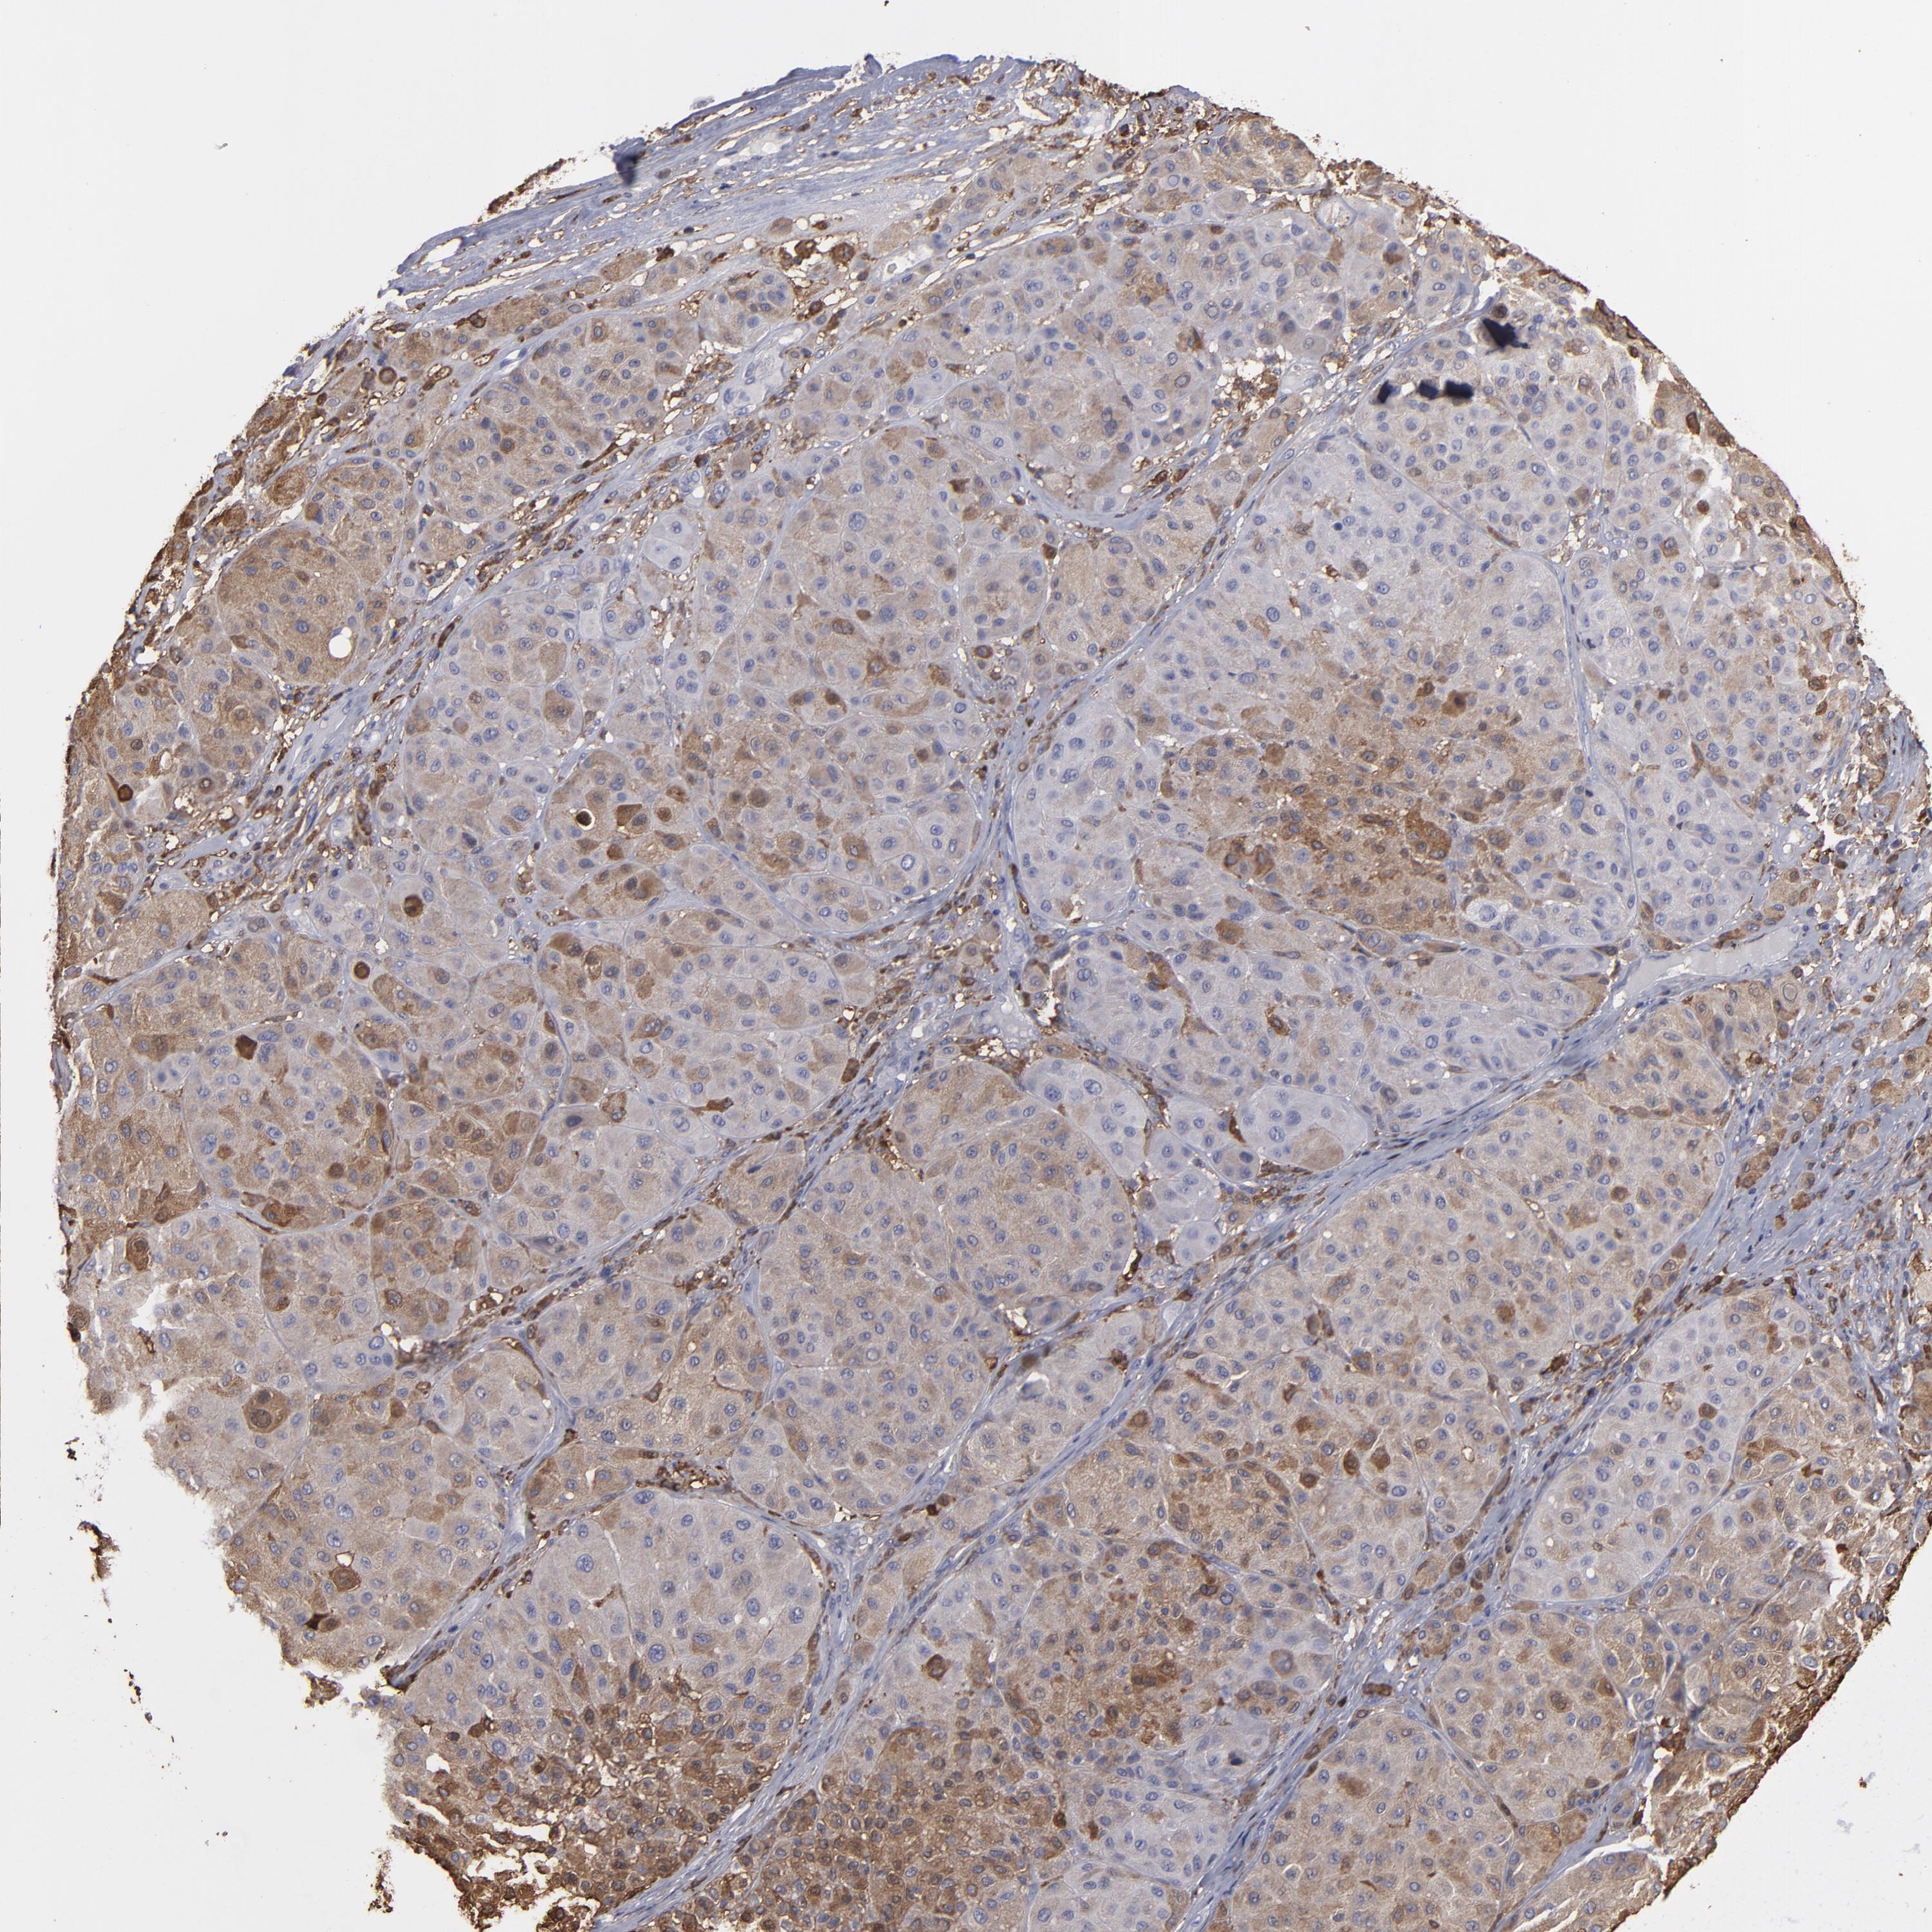

MELANOMA - Protein expressioni

A mouse-over function shows sample information and annotation data. Click on an image to view it in a full screen mode. Samples can be filtered based on level of antibody staining by selecting one or several of the following categories: high, medium, low and not detected. The assay and annotation is described here.

Note that samples used for immunohistochemistry by the Human Protein Atlas do not correspond to samples in the TCGA dataset.

Antibody stainingi

Antibody staining in the annotated cell types in the current human tissue is reported as not detected, low, medium, or high, based on conventional immunohistochemistry profiling in selected tissues. This score is based on the combination of the staining intensity and fraction of stained cells.

Each image is clickable and will lead to virtual microscopy that enables deeper exploration of all samples and also displays staining intensity scores, fraction scores and subcellular localization as well as patient and tissue information for each sample.

Antibody HPA001536

Antibody CAB035996

Staining

High

Medium

Low

Not detected

Intensity

Strong

Moderate

Weak

Negative

Quantity

>75%

75%-25%

<25%

None

Location

Nuclear

Cytoplasmic/membranous

Cytoplasmic/membranous,nuclear

Malignant melanoma, NOS

Malignant melanoma, Metastatic site